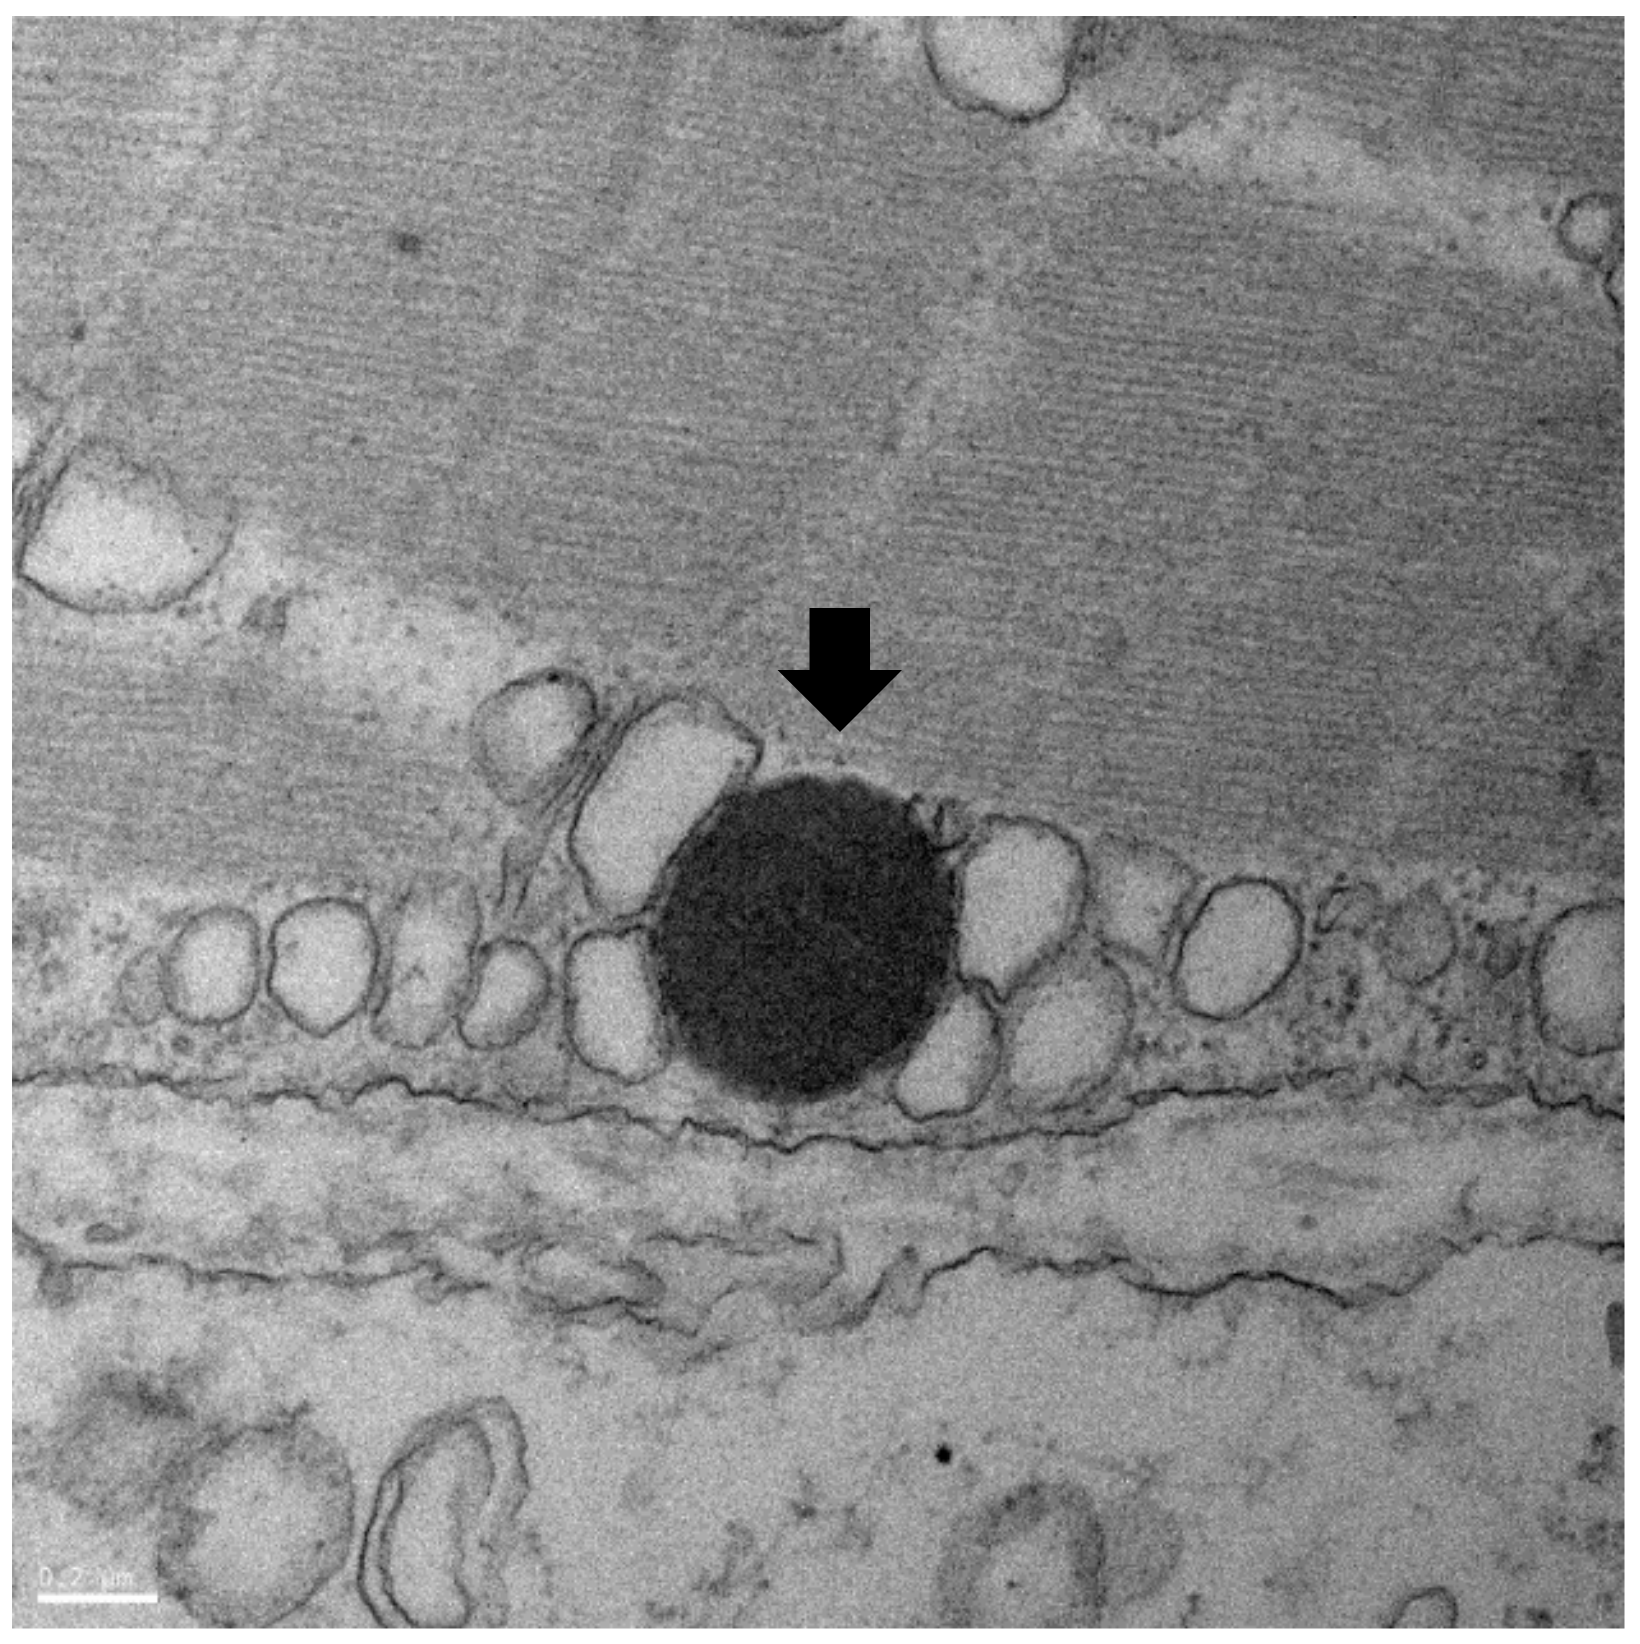

3.4. TEM Analysis